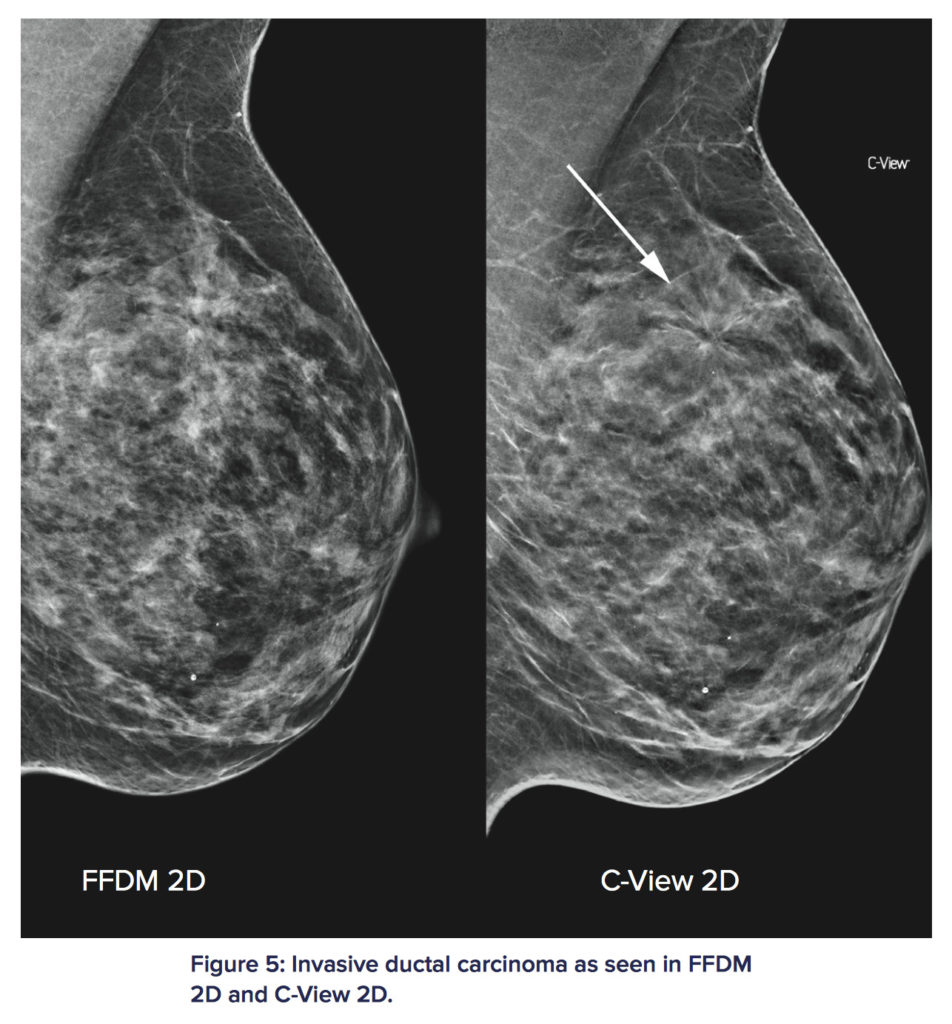

至於呢幅圖呢就顯示指住嗰舊癌,又係C-View完勝。

上圖FFDM 2D即係傳統2D乳房造影直接照出黎嘅片,C-View 2D即係3D後製合成2D片,你係右上角放大嗰度會見到C-View 2D睇鈣化點仲清淅過傳統直出片,真係要寫個服字。